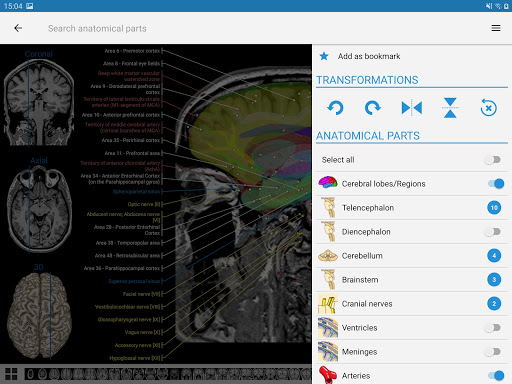

e-Anatomy tiene más de 26 000 imágenes que contienen series de imágenes en vistas axiales, coronales y sagitales, así como radiografías, angiografías, imágenes de disección, gráficos anatómicos e ilustraciones. Todas las imágenes médicas fueron etiquetadas cuidadosamente, más de 967 000 etiquetas disponibles en 12 idiomas, incluida la Terminologia Anatomica latina.

- Toque las etiquetas para mostrar las estructuras anatómicas

- Seleccione las etiquetas anatómicas por categoría

- Localice fácilmente las estructuras anatómicas gracias a la búsqueda de índice